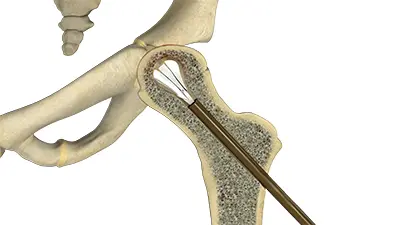

- Core Decompression: A portion of the inner bone is removed to relieve pressure, encourage blood vessel growth, and stimulate new bone formation. In the hip, this is often done through the neck of the femur to the femoral head and can be assisted arthroscopically.

Advantages of Arthroscopic Core Decompression

Dr. Domb and his team often perform AVN treatment using an arthroscopic-assisted approach, which allows for:

- Minimally invasive surgery with smaller incisions

- Direct visualization of the cartilage in the femoral head before performing core decompression

- Precise targeting of the decompression to the affected area

- Safe placement of bone grafts or orthobiologics without entering the joint space

- Simultaneous treatment of other hip issues, such as labral tears or impingement

This approach helps patients preserve their hip joint and improves recovery outcomes while addressing multiple hip issues at once.